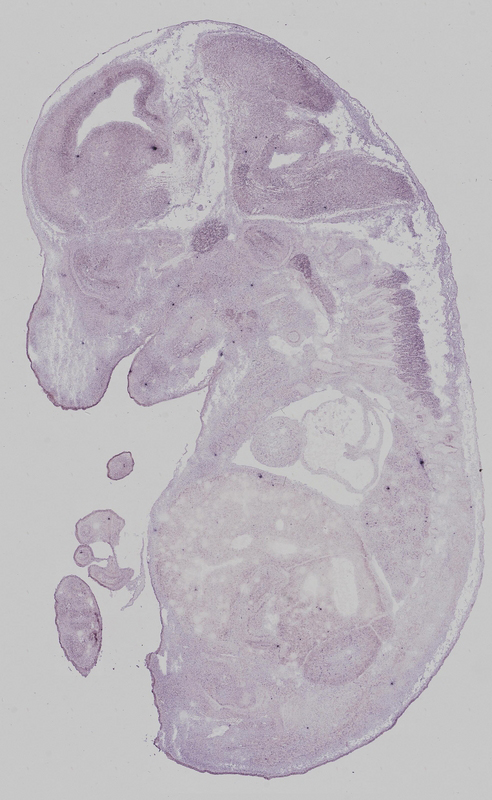

euxassay_002132_10:

embryonic day 14.5

euxassay_002132_11:

euxassay_002132_16:

euxassay_002132_17:

euxassay_002132_18:

euxassay_002132_19: